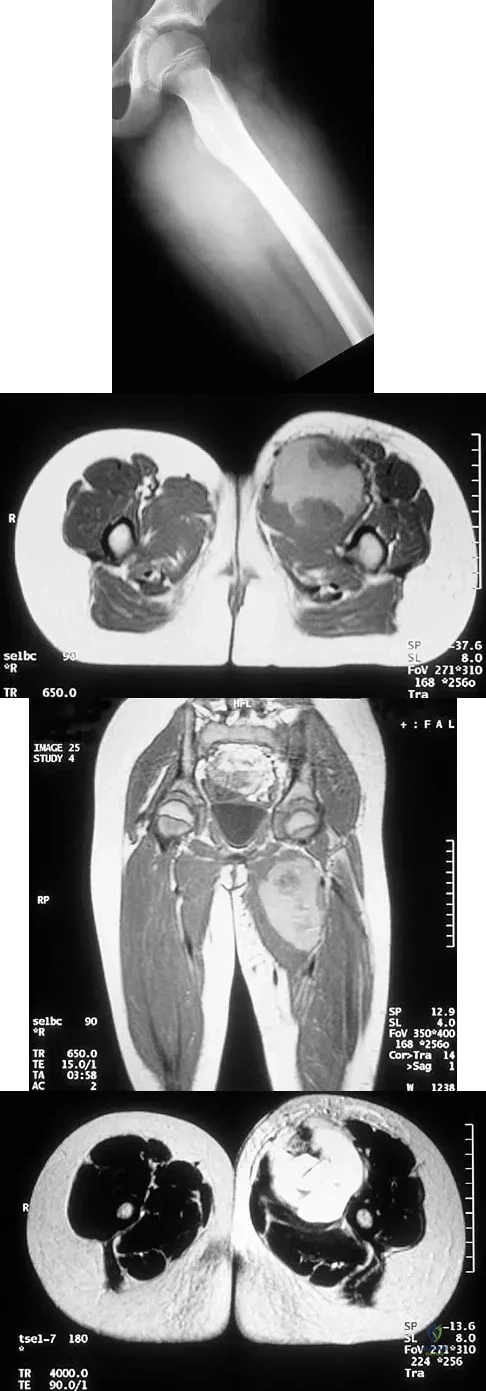

Question 75

An 8-year-old girl has had a painless enlarging mass of insidious onset in the left thigh for the past 3 weeks. Her mother denies any history of trauma, fever, or disease. Examination reveals a nontender, mobile mass in the left medial thigh. Her gait is normal. Figures 25a through 25d show the frog-lateral radiograph, the axial and coronal T1-weighted MRI scans, and the axial T2-weighted MRI scan. Biopsy results reveal a nonrhabdomyosarcoma soft-tissue sarcoma. The most appropriate treatment should consist of

Explanation

Question 82 High Yield

Figures 52a and 52b show the radiographs of a left proximal femoral lesion noted serendipitously following minor trauma to the left hip. The patient has no thigh pain and is fully active without limitation. What is the most likely diagnosis of this bony lesion?

Detailed Explanation